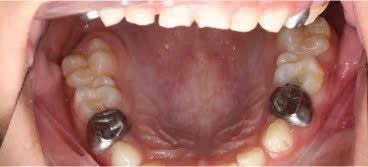

SSC (Stainless Steel Crown) là mão răng bằng thép không gỉ, được thiết kế sẵn với nhiều kích cỡ khác nhau, thường dùng để phục hồi răng sữa đã bị sâu lớn hoặc tổn thương nặng. Đây là một dạng phục hình toàn phần bao phủ toàn bộ thân răng, giúp bảo tồn và duy trì chức năng của răng sữa cho đến khi thay răng vĩnh viễn.

Mão SSC giúp bao phủ toàn bộ thân răng, giảm nguy cơ nứt vỡ và tái nhiễm khuẩn.